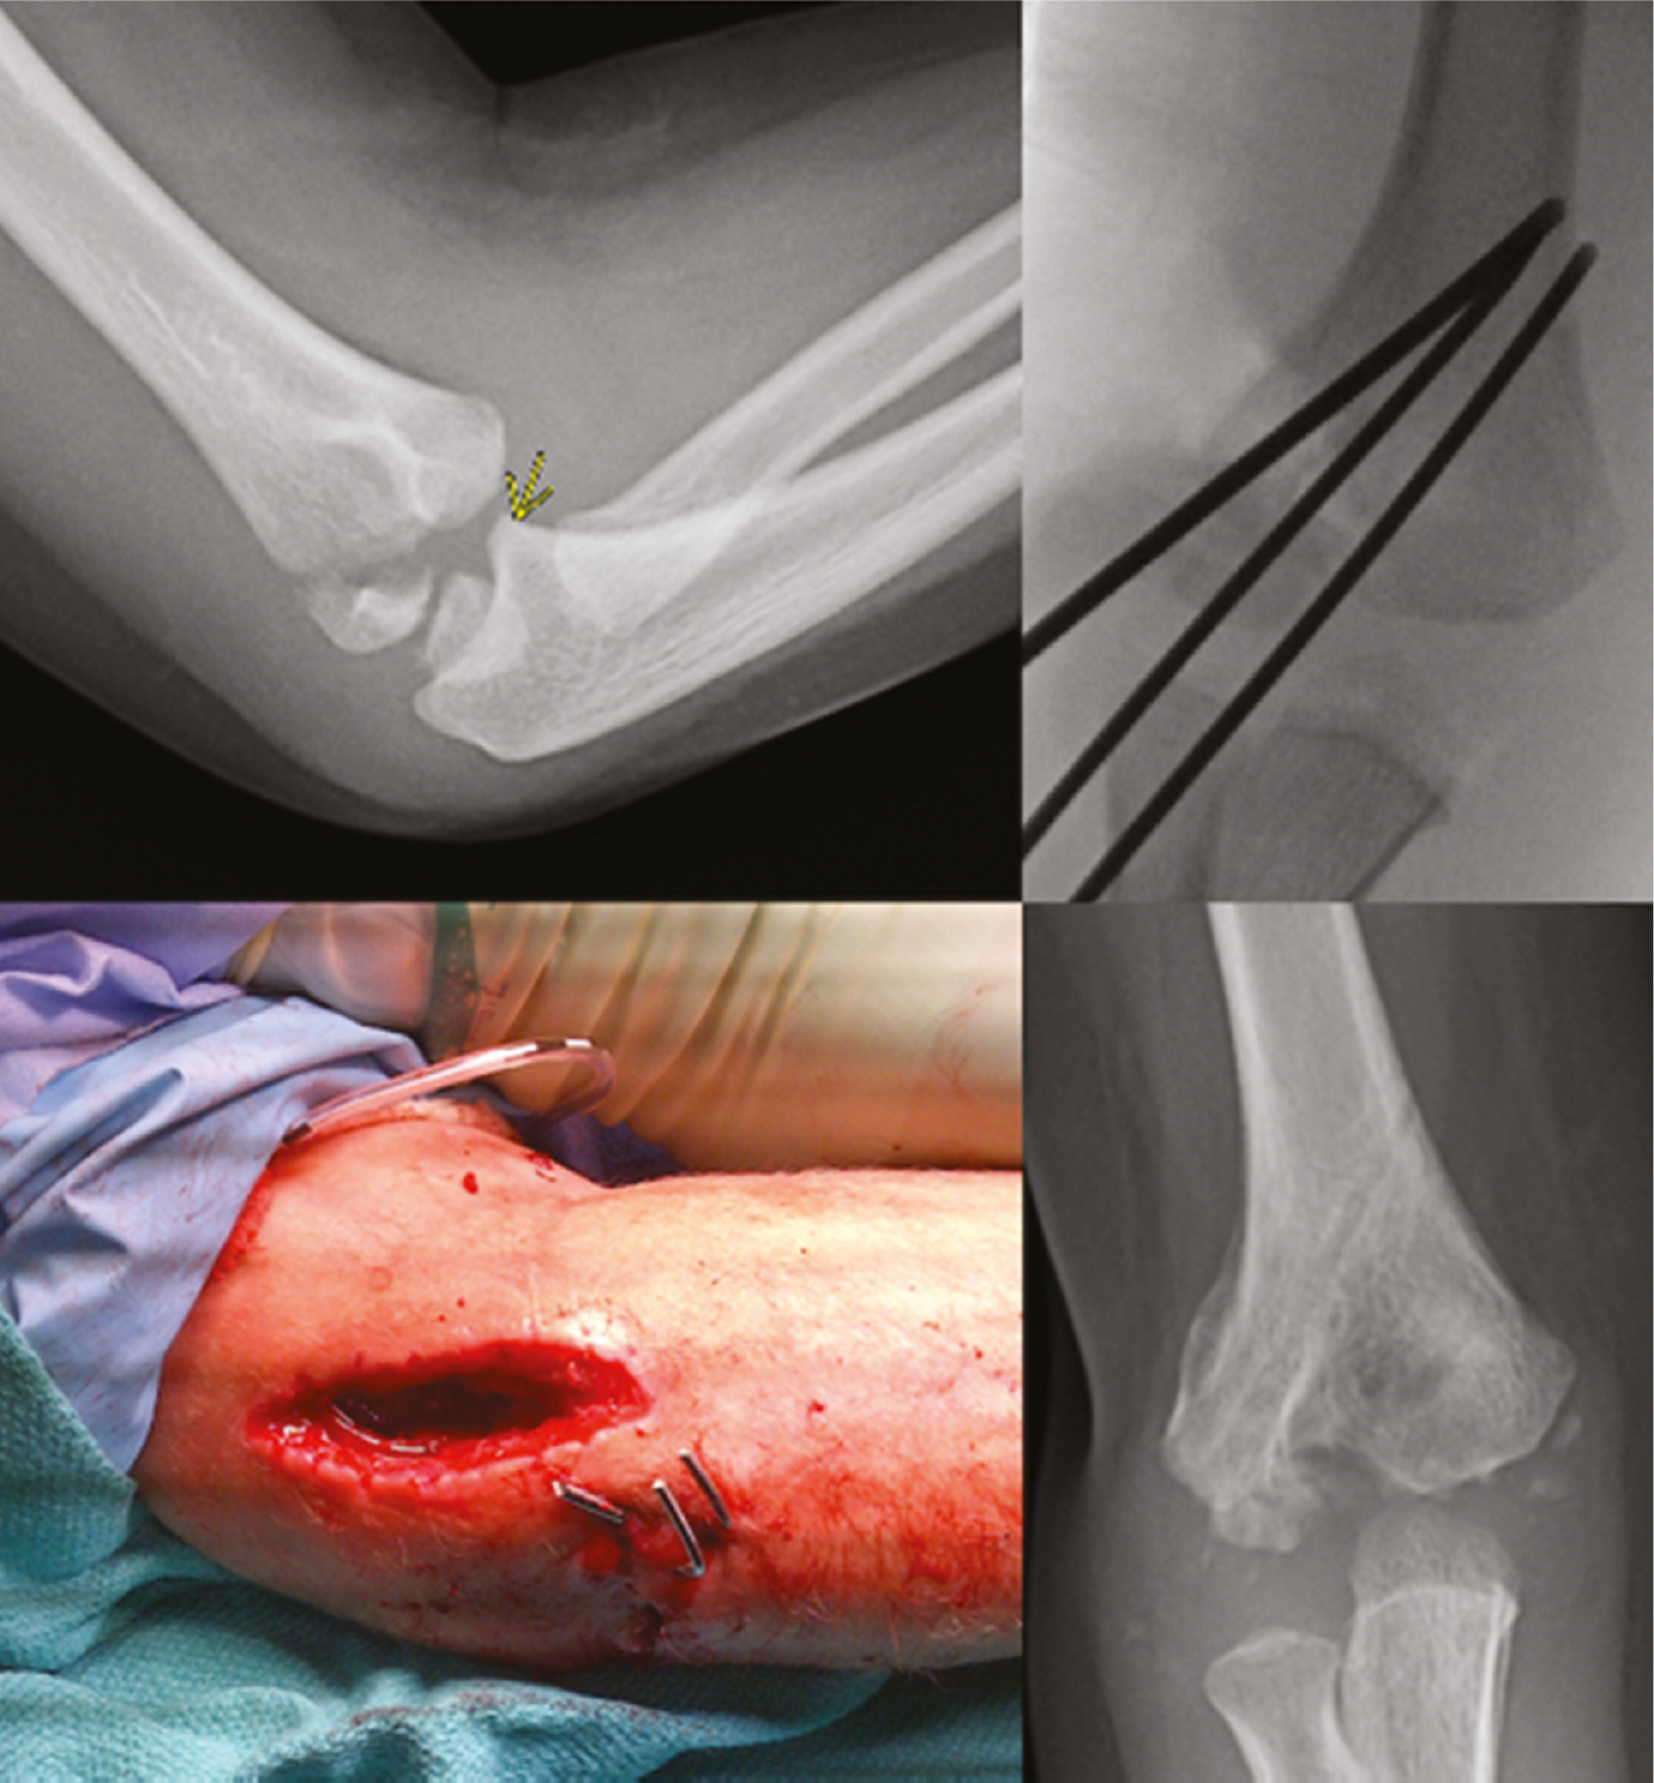

One complication that can occur from lateral condyle fracture pinning is septic arthritis developing from pin tract infection. It’s prudent to remember that pins used to stabilize these fractures are very commonly intraarticular; thus, pin tract inflammation/infection can lead to septic arthritis. For this reason, these pins are ideally removed within 4 weeks regardless of radiographic signs of healing (Figure 16).

Figure 16. This 5-year-old boy with a lateral condyle fracture developed septic arthritis and despite eventual healing, has signs of central humerus necrosis with an unknown natural history.

Most lateral condyle fractures result from a fall on the outstretched upper extremity and the varus force leads the extensor mechanism to pull the lateral condyle off to varying degrees. Minimally displaced fractures (2–4 mm) will hinge laterally and have an intact or minimally displaced articular surface that can prevent displacement and facilitate reduction with direct pressure (Figure 1).

Figure 1. The vast majority of lateral condyle fractures result from avulsion of the lateral condyle with the arm in varus. Minimally displaced fractures may have an intact or minimally displaced articular hinge that facilitates closed reduction (red bracket). While an archaic classification, this fracture represents a Milch 2 fracture.

Rarely does a lateral condyle fracture result from an axial load in valgus that shears the lateral condyle proximally and always disrupts the articular surface (Figure 2). These are much harder to reduce closed and are more likely to require open reduction and internal fixation.

Figure 2. This intraarticular fracture (left) is likely a result of an axial load in valgus and can shear the lateral condyle off. Note the lateral elbow swelling. One year after closed treatment (right), the fracture has healed but is in slight cubitus varus. This would correspond to a Milch 1 fracture.